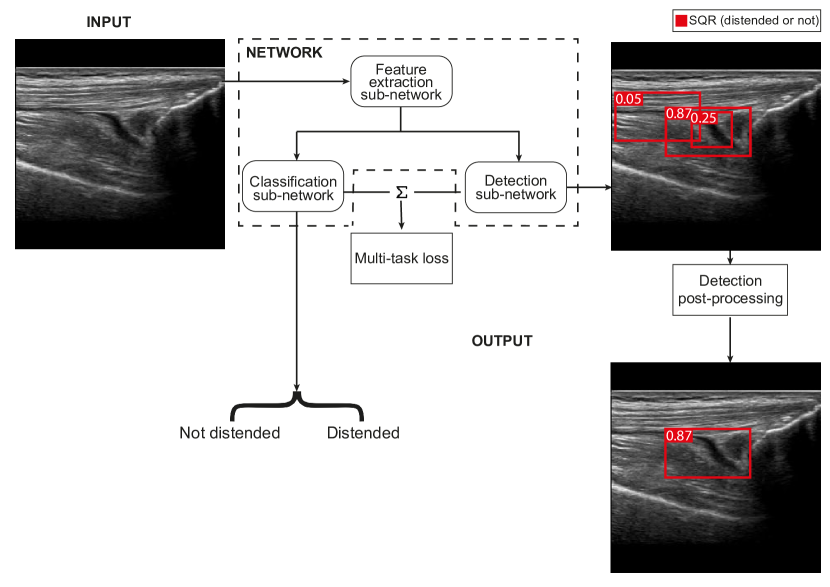

4.2 Multi-task approach

The Detection approach addresses the problem of classifying the SQR as distended or not by selecting the label of the detection with the highest confidence. An alternative (and possibly more natural) solution would be to classify the entire image. However, this would not provide the needed SQR bounding box. For this reason we propose the Multi-task Approach that pairs image classification and detection.

Refer to caption

Figure 4: Overall architecture of the Multi-task approach

The proposed network is a modified version of the network used for the Detection approach. The key modification consists of a Classification sub-network that performs the SQR binary classification. The input image is first processed by the Feature Extraction sub-network, that is shared for both classification and detection tasks. Then the extracted features are simultaneously processed by the Detection sub-network and the Classification sub-network. The Classification sub-network processes the features and returns the predicted SQR class (i.e., distended or not) considering the whole image.

Differently from the Detection Approach solution, the goal of the Detection sub-network in the Multi-task solution is simply to detect the SQR, without providing information about the distension. Hence, the Detection sub-network network is trained with a single class and it returns a set of bounding boxes, all belonging to the same class, each with an associated confidence value. The Detection Post-processing module selects the bounding box with the highest confidence. During the training phase, the multi-task loss jointly considers the errors on classification and detection to update the network weights.